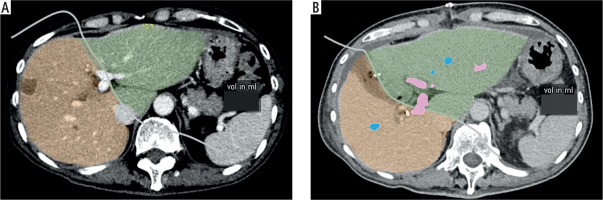

Study variables include age, gender, comorbidities, clinical presentation, pre-operative investigations (biochemical investigations and ICG-R15), CT volumetry (residual liver volume (RLV), standardized liver volume (SLV), and standardized future liver remnant (sFLR), histopathology findings and intra-operative findings (estimated blood loss, length of operation). SLV (ml) was calculated using the Chengdu formula: 11.508 × body weight (kg) + 334.024 [12]. sFLR is defined as the ratio of RLV to SLV. Figure 1A and B shows the method of calculation of the RLV of one of the included patients before stage 1 ALPPS and after stage 1 ALPPS respectively. Short-term study outcomes include the length of hospitalization stay (LOS), post-operative morbidity, 30-day readmission and 30-day mortality. Post-operative morbidity was defined as occurrence of any of the following post-operative complications: PHLF, intra-abdominal collection, pneumonia, pleural effusion, surgical site infection and ileus. 30-day readmission and 30-day mortality were defined as readmission or mortality, respectively, within 30 days from the date of stage 2 ALPPS. PHLF was defined as per the International Study Group of Liver Surgery (ISGLS)’s consensus in 2011 [13]. Long-term study outcomes include length of follow-up, presence of local recurrence, distant recurrence, overall survival (OS) and disease-free survival (DFS). OS and DFS were defined as the percentage of alive or disease-free patients, respectively, at the end of the study, i.e. January 2022.

Median serum total bilirubin on POD5 following stage 1 ALPPS was 13 µmol/l (range 7-24). Table 3 summarizes ICG-R15 and CT volumetry findings pre-operatively and after stage 1 ALPPS. Median time of pre-operative ICG-R15 and CT volumetry prior to stage 1 ALPPS was 9 days (range 2-30) and 32.5 days (range 3-78) respectively. Median time of ICG-R15 and CT volumetry after stage 1 ALPPS was 6.5 days (range 5-9) and 7 days (range 6-8) respectively. The median time of ICG-R15 and CT volumetry between after stage 1 ALPPS and stage 2 ALPPS was 2 days (range 1-3) and 1 day (range 1-4) respectively.